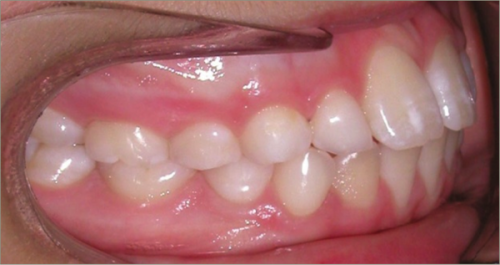

12 year old female:

Diagnosis:

- Missing upper right lateral incisor & lower right cuspid

- Horizontally impacted lower left cuspid

- Peg shaped upper left lateral incisor

Treatment:

- Extraction of impacted lower left cuspid, and peg shaped upper left lateral incisor

- Upper cuspids substituted as laterals

- Full fixed appliances

- 20 months